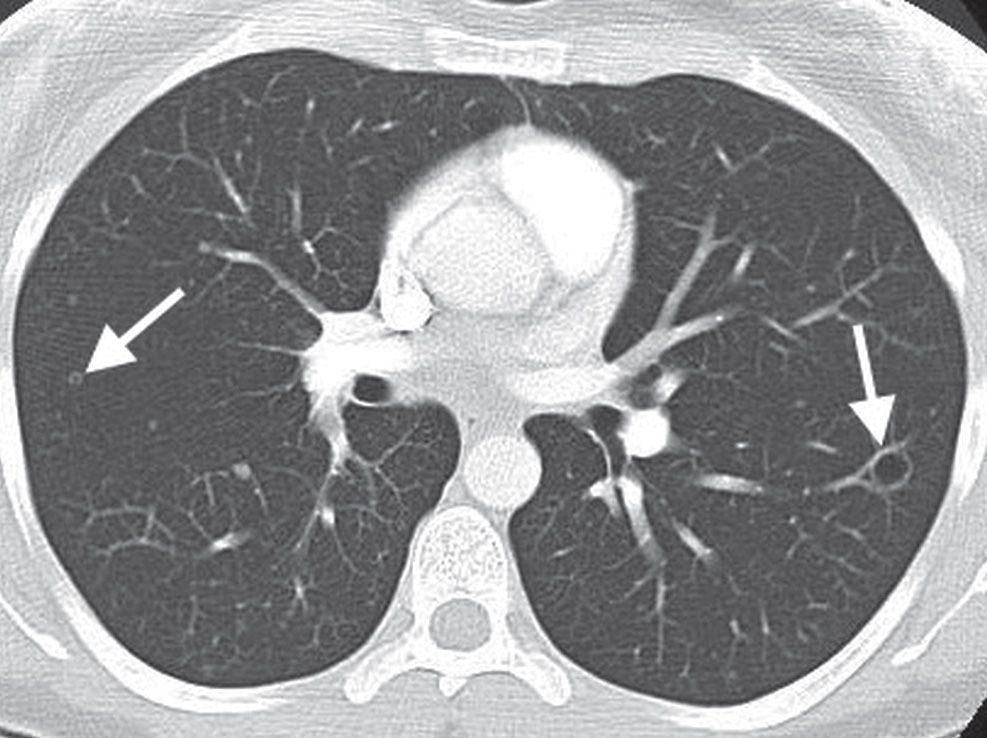

The differential on this ct includes multifocal adenocarcinoma, vasculitis, metastases and cavitating infection. The american lung association connects patients, families, friends and caregivers for support and inspiration as they face lung cancer. Staging is an important first step in the management of.

Multiple lung nodules have also been seen with metastases from medullary thyroid cancer, melanoma, and squamous cell cancers of the head and neck, among others. Multifocal lung cancers appear to originate from single cancer clone multiple, anatomically distinct lung cancer tumours may frequently arise from a single cancer cell,. Background data and proposals for the application of tnm staging rules to lung cancer presenting as multiple nodules with ground.